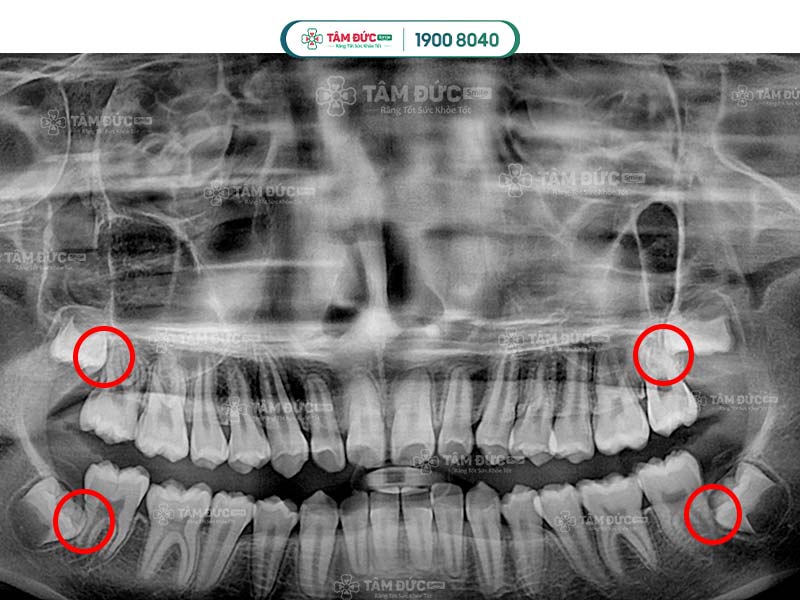

Dấu hiệu nhận biết Quý khách có răng khôn mọc lệch 45 độ là các cơn đau âm ỉ, kéo dài nhiều ngày. Nguyên nhân là vì khoảng trống trên hàm đã không còn nhiều, vị trí của răng khôn bị ảnh hưởng bởi mô mềm và răng hàm số 7. Điều này đã làm răng mọc nghiêng theo nhiều góc độ so với răng số 7 như 45 độ hay 90 độ.

Bước 2: Đối với răng khôn mọc lệch, Quý khách cần được chụp X-Quang để xác định hướng mọc, vị trí của chân răng, xương hàm và dây thần kinh.